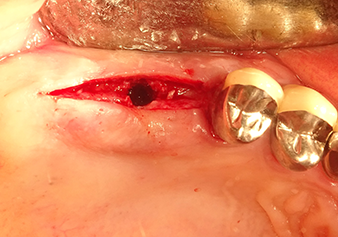

A 49-year-old female patient, a non-smoker and with nothing remarkable in her general medical history, was referred to our oral surgery practice for surgical extraction of tooth 16 and subsequent implantation. After the extraction, the patient experienced mild sinusitis trouble with the resultthat we initially waited six months before carrying out the measure. The residual bone height at the planned implant position measured 3-4 mm (Fig. 1 and 2).

Following atraumatic preparation of the mucoperiosteal flap, the implant position was marked with the I1 instrument and the site prepared – until initial resistance was felt. Piezosurgical instruments were used in an up and down movement without any pressure being exerted. The piezoelectric vibration produced the desired and efficient cavitation.